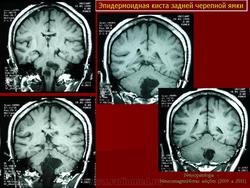

Эпидермоидные кисты задней черепной ямки

Эпидермоидные кисты задней черепной ямки - редкие новообразования. По данным Института нейрохирургии они составляют 0.5% от всех опухолей центральной нервной системы. Формирование морфологического субстрата эпидермоидных кист происходит на 3 неделе внутриутробной жизни, вследствие нарушения эмбриогенеза и смещения эпителиальной ткани в нервную трубку.

С 1985 по 2000 г.г. в НИИ нейрохирургии им. Н.Н. Бурденко обследовано и оперировано 78 больных с эпидермоидными кистами задней черепной ямки. Изучен клинический симптомокомплекс и КТ, МРТ картина эпидермоидных кист задней черепной ямки.

Качество оперативного лечения оценивалось изучением динамики неврологического статуса, данных КТ, МРТ, как до операции, так и после операции на разных его стадиях. Современные радиологические исследования и микрохирургическая техника полностью обеспечивает радикальное удаление эпидермоидных кист с хорошим после операционным результатом.